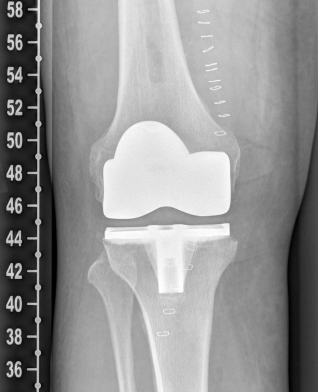

Example X-ray images before and after implantation of a Persona knee prosthesis with robot.

| b) nach Implantation der Knie-Totalendoprothese angefertigte Röntgenaufnahmen | |